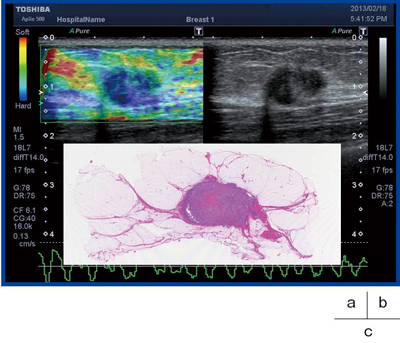

69歳,女性。右乳房の腫瘤は非常に低エコーな腫瘤で,エラストグラフィでは硬さがないことが表現されている。病理像から,細胞成分に富むトリプルネガティブ乳がんであった(図8)。

図8 症例3:エラストグラフィ(a)

b:Bモード画像,c:病理組織像